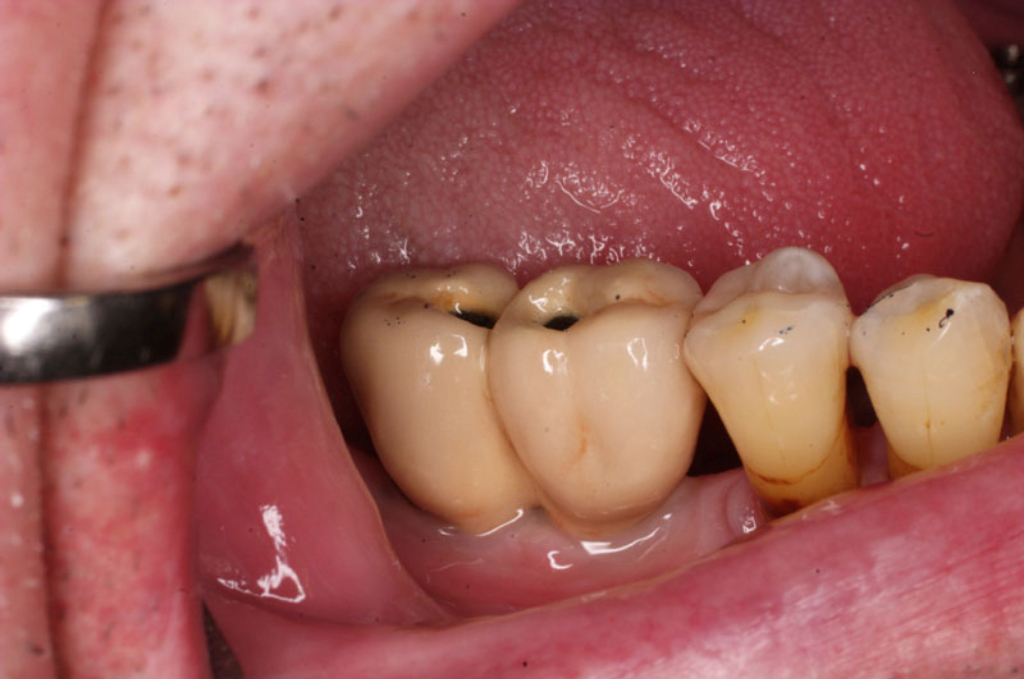

Náhrada jednoho zubu pomocí implantátu je možná také v postranním úseku chrupu. Při ztrátě většího počtu zubů ve frontálním nebo postranním úseku může být mezer uzavřena větším počtem jednotlivých implantátů.

Při ošetření pomocí jednotlivých implantátů zůstávají sousední zuby neporušené – intaktní. Při klasickém ošetření pomocí můstků musejí být tyto zuby obroušeny!